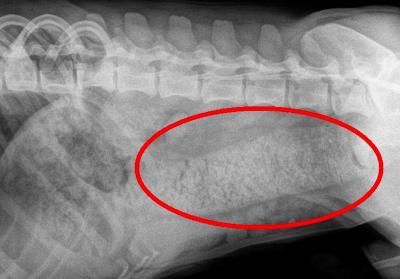

Druhý případ byl již od počátku zapeklitý. Pitbulteriérka Zuzanka (22 kg) přišla na kliniku až čtvrtý den, co měla problémy. Majitel se dušoval, že kosti nedává - přesto jsme na rentgenu odhalili přítomnost cizího tělesa v jícnu (těleso mělo na RTG strukturu kosti).

Stav byl velmi komplikovaný lokalizací cizího tělesa - kost byla uvízlá v jícnu v hrudníku kousek od srdce.

Na snímku vidíte onu kost. Všemi třemi ostrými okraji byla zaříznuta do stěny jícnu. Vzhledem ke špatné prognóze (zúženiny jícnu a nemožnost přijímat potravu) proto bylo nakonec nutno k naší velké lítosti provést euthanasii.